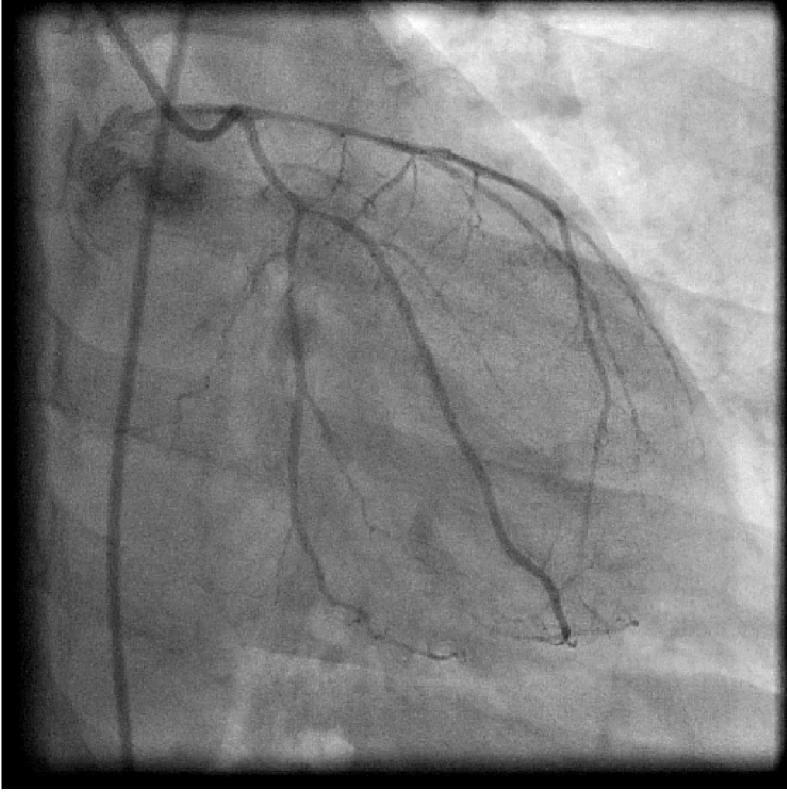

We present a 42-year-smoker man without any medical problem who developed syncope. Coronary angiography revealed diffuse significant narrowing of proximal left anterior descending artery (LAD), 90% osteal stenosis of large obtuse marginal (OM), 90% diffuse narrowing of proximal right coronary artery (RCA), which was relieved by intracoronary administration of nitrate. He was discharged on calcium channel blockers and nitrates but one month later developed syncope again and died.

我们报告一名42岁的男性吸烟者,他没有任何医学问题,但出现了晕厥。冠状动脉造影显示左前降支近端弥漫性显著狭窄,大钝缘支骨部狭窄90%,右冠状动脉近端弥漫性狭窄90%,冠状动脉内注射硝酸盐后狭窄缓解。他出院时服用钙通道阻滞剂和硝酸盐,但一个月后再次出现晕厥并死亡。